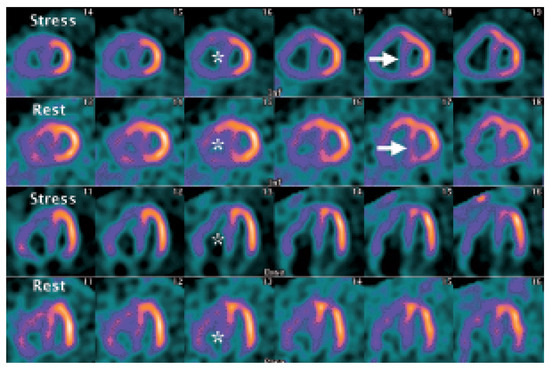

Myocardial Perfusion SPECT Features of Severe Pulmonary Artery Hypertension

by Micha T. Maeder, Martin Stöckli and Michael J. Zellweger

A 49-year-old man with a history of sarcoidosis and associated severe pulmonary hypertension was referred for myocardial perfusion imaging (MPI) because of preoperative workup (planed lung transplant) [...] Full article